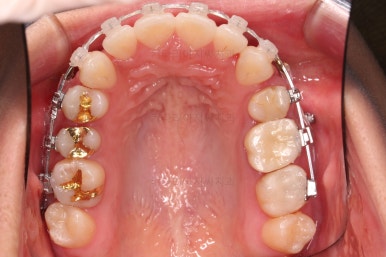

어느새 틈도 다 닫히고요.

마무리 과정만 남았습니다.

틈이 다 없어졌고, 교합도 양호합니다.

무엇보다 임플란트 없이 결손부위가 깔끔하게 채워졌고요.

매우 다행으로 사랑니도 다 있었기 때문에 마치 큰 어금니가 다 있는 것과 같은 상황이 되었습니다.

총 치료기간도 2년 반, 30개월이 걸렸습니다.

3년 이상 봐야 되는 부산사랑니교정 치료라고 말씀 드리고 시작했음에도 예상보다 훨씬 빨리 종료 되어 매우 만족스러운 치료였습니다.

전후 비교 해볼게요.

입안의 모습은 더할나위 없이 잘 개선되었고요.

상하좌우 이 뽑은 위치와 크기가 달라 이정도 중앙선은 매우 잘 맞는 상황인거고요.